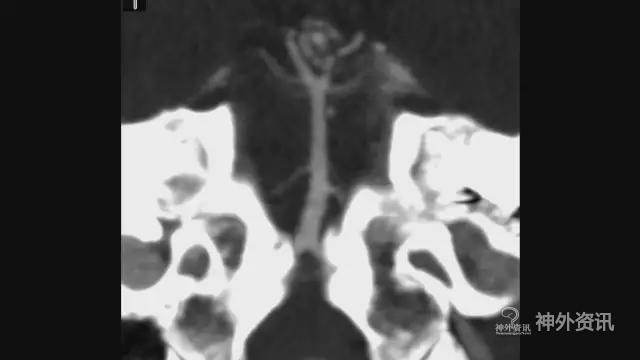

图4. 基底动脉干动脉瘤(瘤颈低于后床突1cm)。

图5. 基底动脉干动脉瘤(瘤颈低于后床突1cm)。

此例基底动脉干动脉瘤位置很低,选择相对费时的乙状窦前入路,开颅时注意保护横窦及乙状窦;在岩上窦两侧及乙状窦前剪开硬膜,缝扎岩上窦,切开小脑幕,瘤颈近心端远心端分别予以临时阻断;仔细分离瘤颈,由于为微小动脉瘤,应用下文介绍的二次夹闭技术予以夹闭。